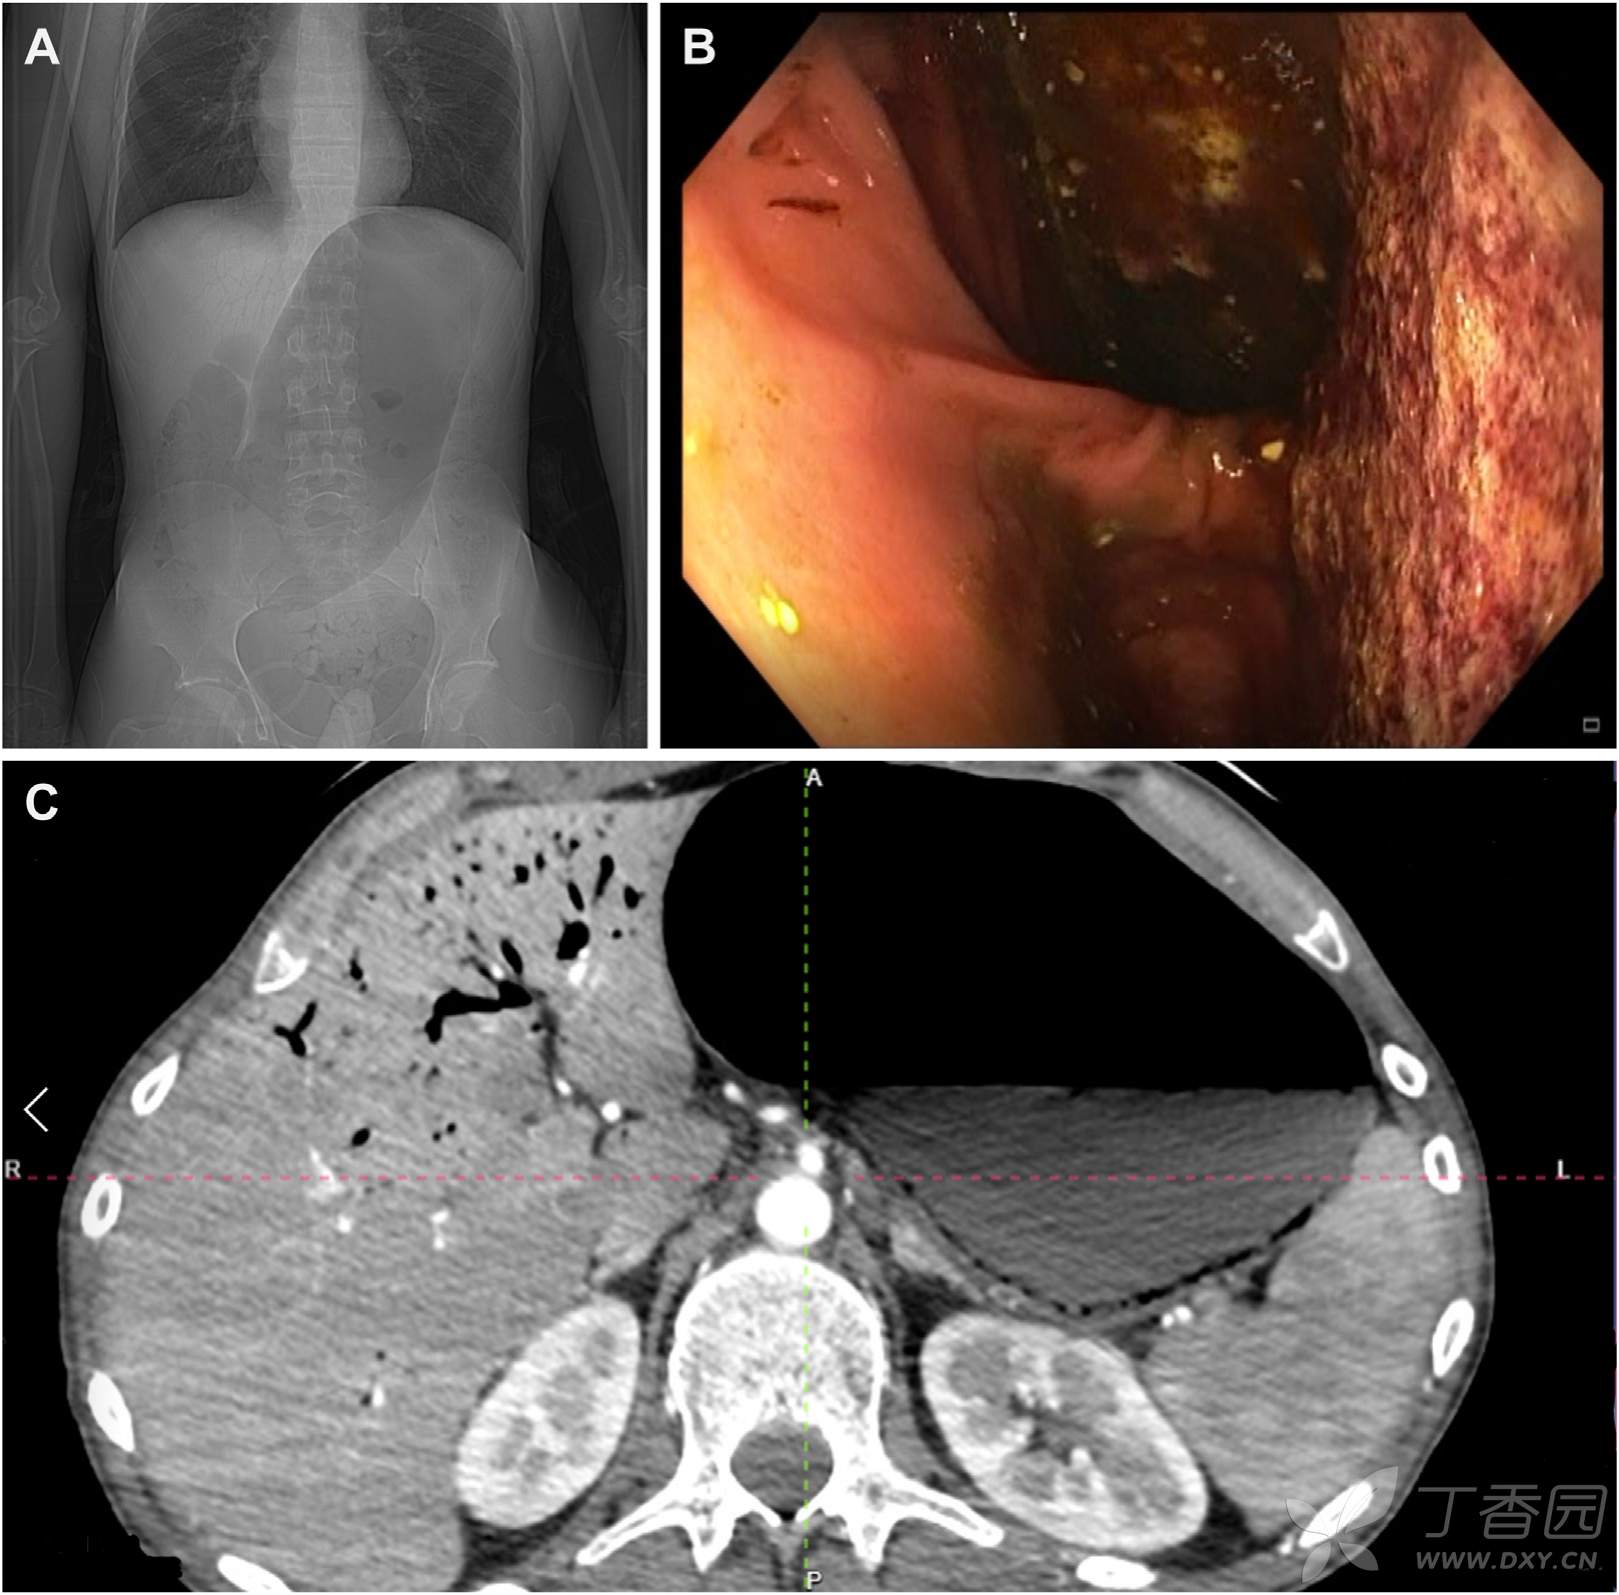

辅助检查:WBC正常,CRP128.7 mg/L (正常<5 mg/L) 。腹部B超因气体过多观察不清,疑诊结肠扭转。腹部平片如图A。胃镜所见如图B。腹部CT及血管成像如图C。